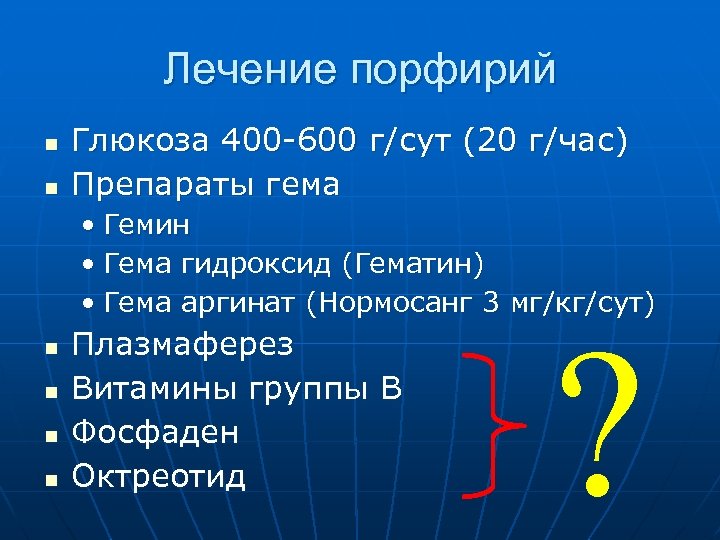

Лечение порфирий n n Глюкоза 400 -600 г/сут (20 г/час) Препараты гема • Гемин • Гема гидроксид (Гематин) • Гема аргинат (Нормосанг 3 мг/кг/сут) n n Плазмаферез Витамины группы В Фосфаден Октреотид ?